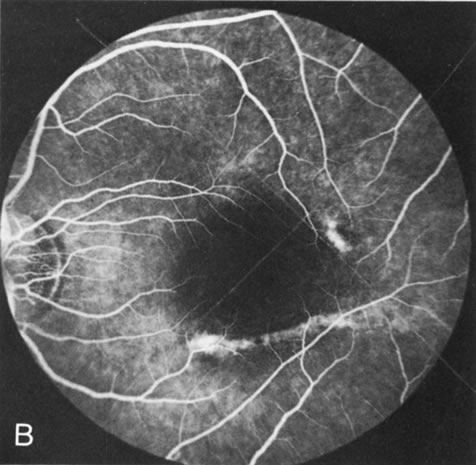

In retinitis pigmentosa (RP), the pigment abnormalities of atrophy, migration, and clumping are made apparent by transmitted hyperfluorescence and blocked hypofluorescence (Fig. 1A). Patients who have very minimal pigmentary alterations (pauci pigmentary RP) or no pigment abnormalities (RP sine pigmento) may show the abnormalities on fluorescien angiography (FA). It is uncommon to see choriocapillaris atrophy except in the late stages. This finding corresponds to the histopathology, which shows that the earliest abnormalities are in the photoreceptors and that the choroid is normal.1

Fig. 1. Retinitis pigmentosa. A. A typical area of bone spicule pigmentation. B. Diffuse dye leakage is apparent throughout the posterior pole. C. The early angiogram shows dilated and irregular retinal radial peripapillary capillaries and perifoveal retinal capillaries. D. Leakage from these vessels are evident in the late angiogram.

Dye leakage in RP may occur from the retinal vessels or at the level of the retinal pigment epithelium (Fig. 1B).2–4 The leakage may be seen in the macula and posterior pole, along the vascular arcades in the distribution of the radial peripapillary capillaries, and in the periphery (where an exudative vasculopathy resembling Coats' disease is suggested).

Of more clinical importance is the role of FA in the diagnosis and treatment of cystoid macular edema (CME) (Fig. 1C and D). Stereoscopic FA indicates that the leakage, which may be diffuse or have the typical petaloid stellate appearance of CME, can come from the perifoveal retinal capillaries, from the choroid through the RPE, or from a combination of both sources.4 With the recent suggestion that CME in RP may be successfully treated with acetazolamide,5, 6 FA is thus important to document the diagnosis of CME, establish the origin(s) of leakage, and follow patients during and after therapy.